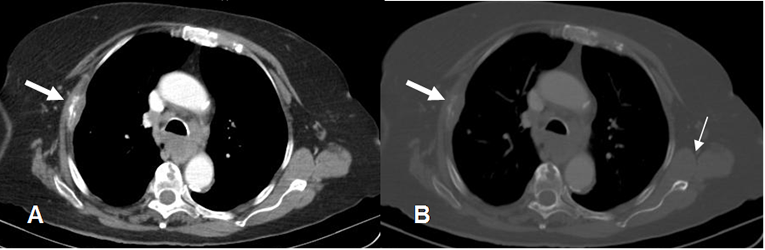

Fig 220 B. Metástasis subcutánea.

A y B: TAC axial con contraste. Neoplasia pulmonar central izquierda, con derrames pleurales bilaterales, adenopatías mediastinales e hiliares contralaterales. En B se encuentra imagen redondeada y superficial en los tejidos blandos, que corresponde a metástasis subcutánea.